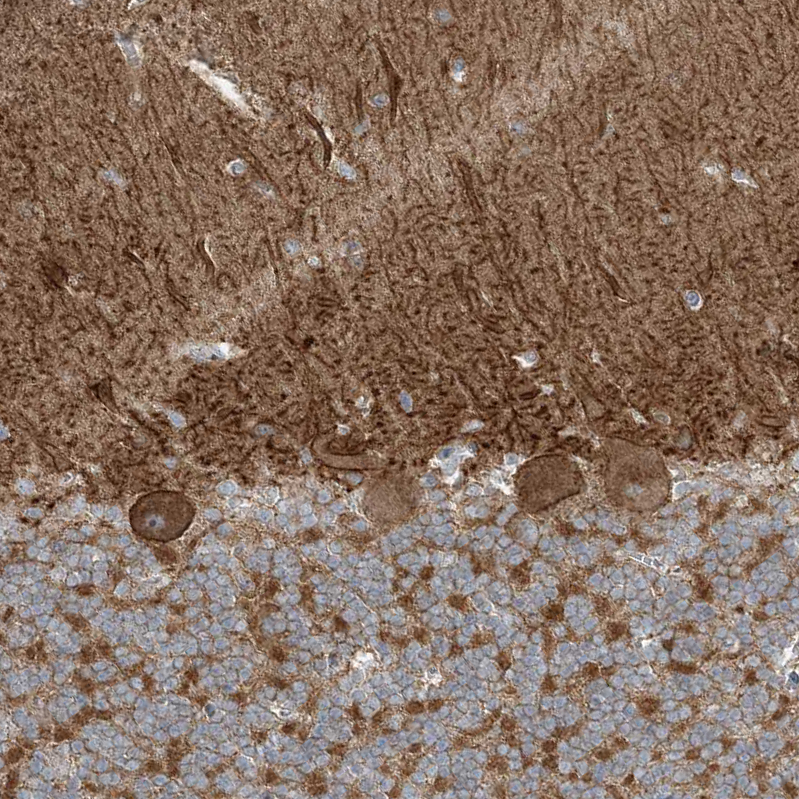

Immunohistochemistry analysis in human cerebral cortex and lymph node tissues using HPA034755 antibody. Corresponding SLC4A10 RNA-seq data are presented for the same tissues.